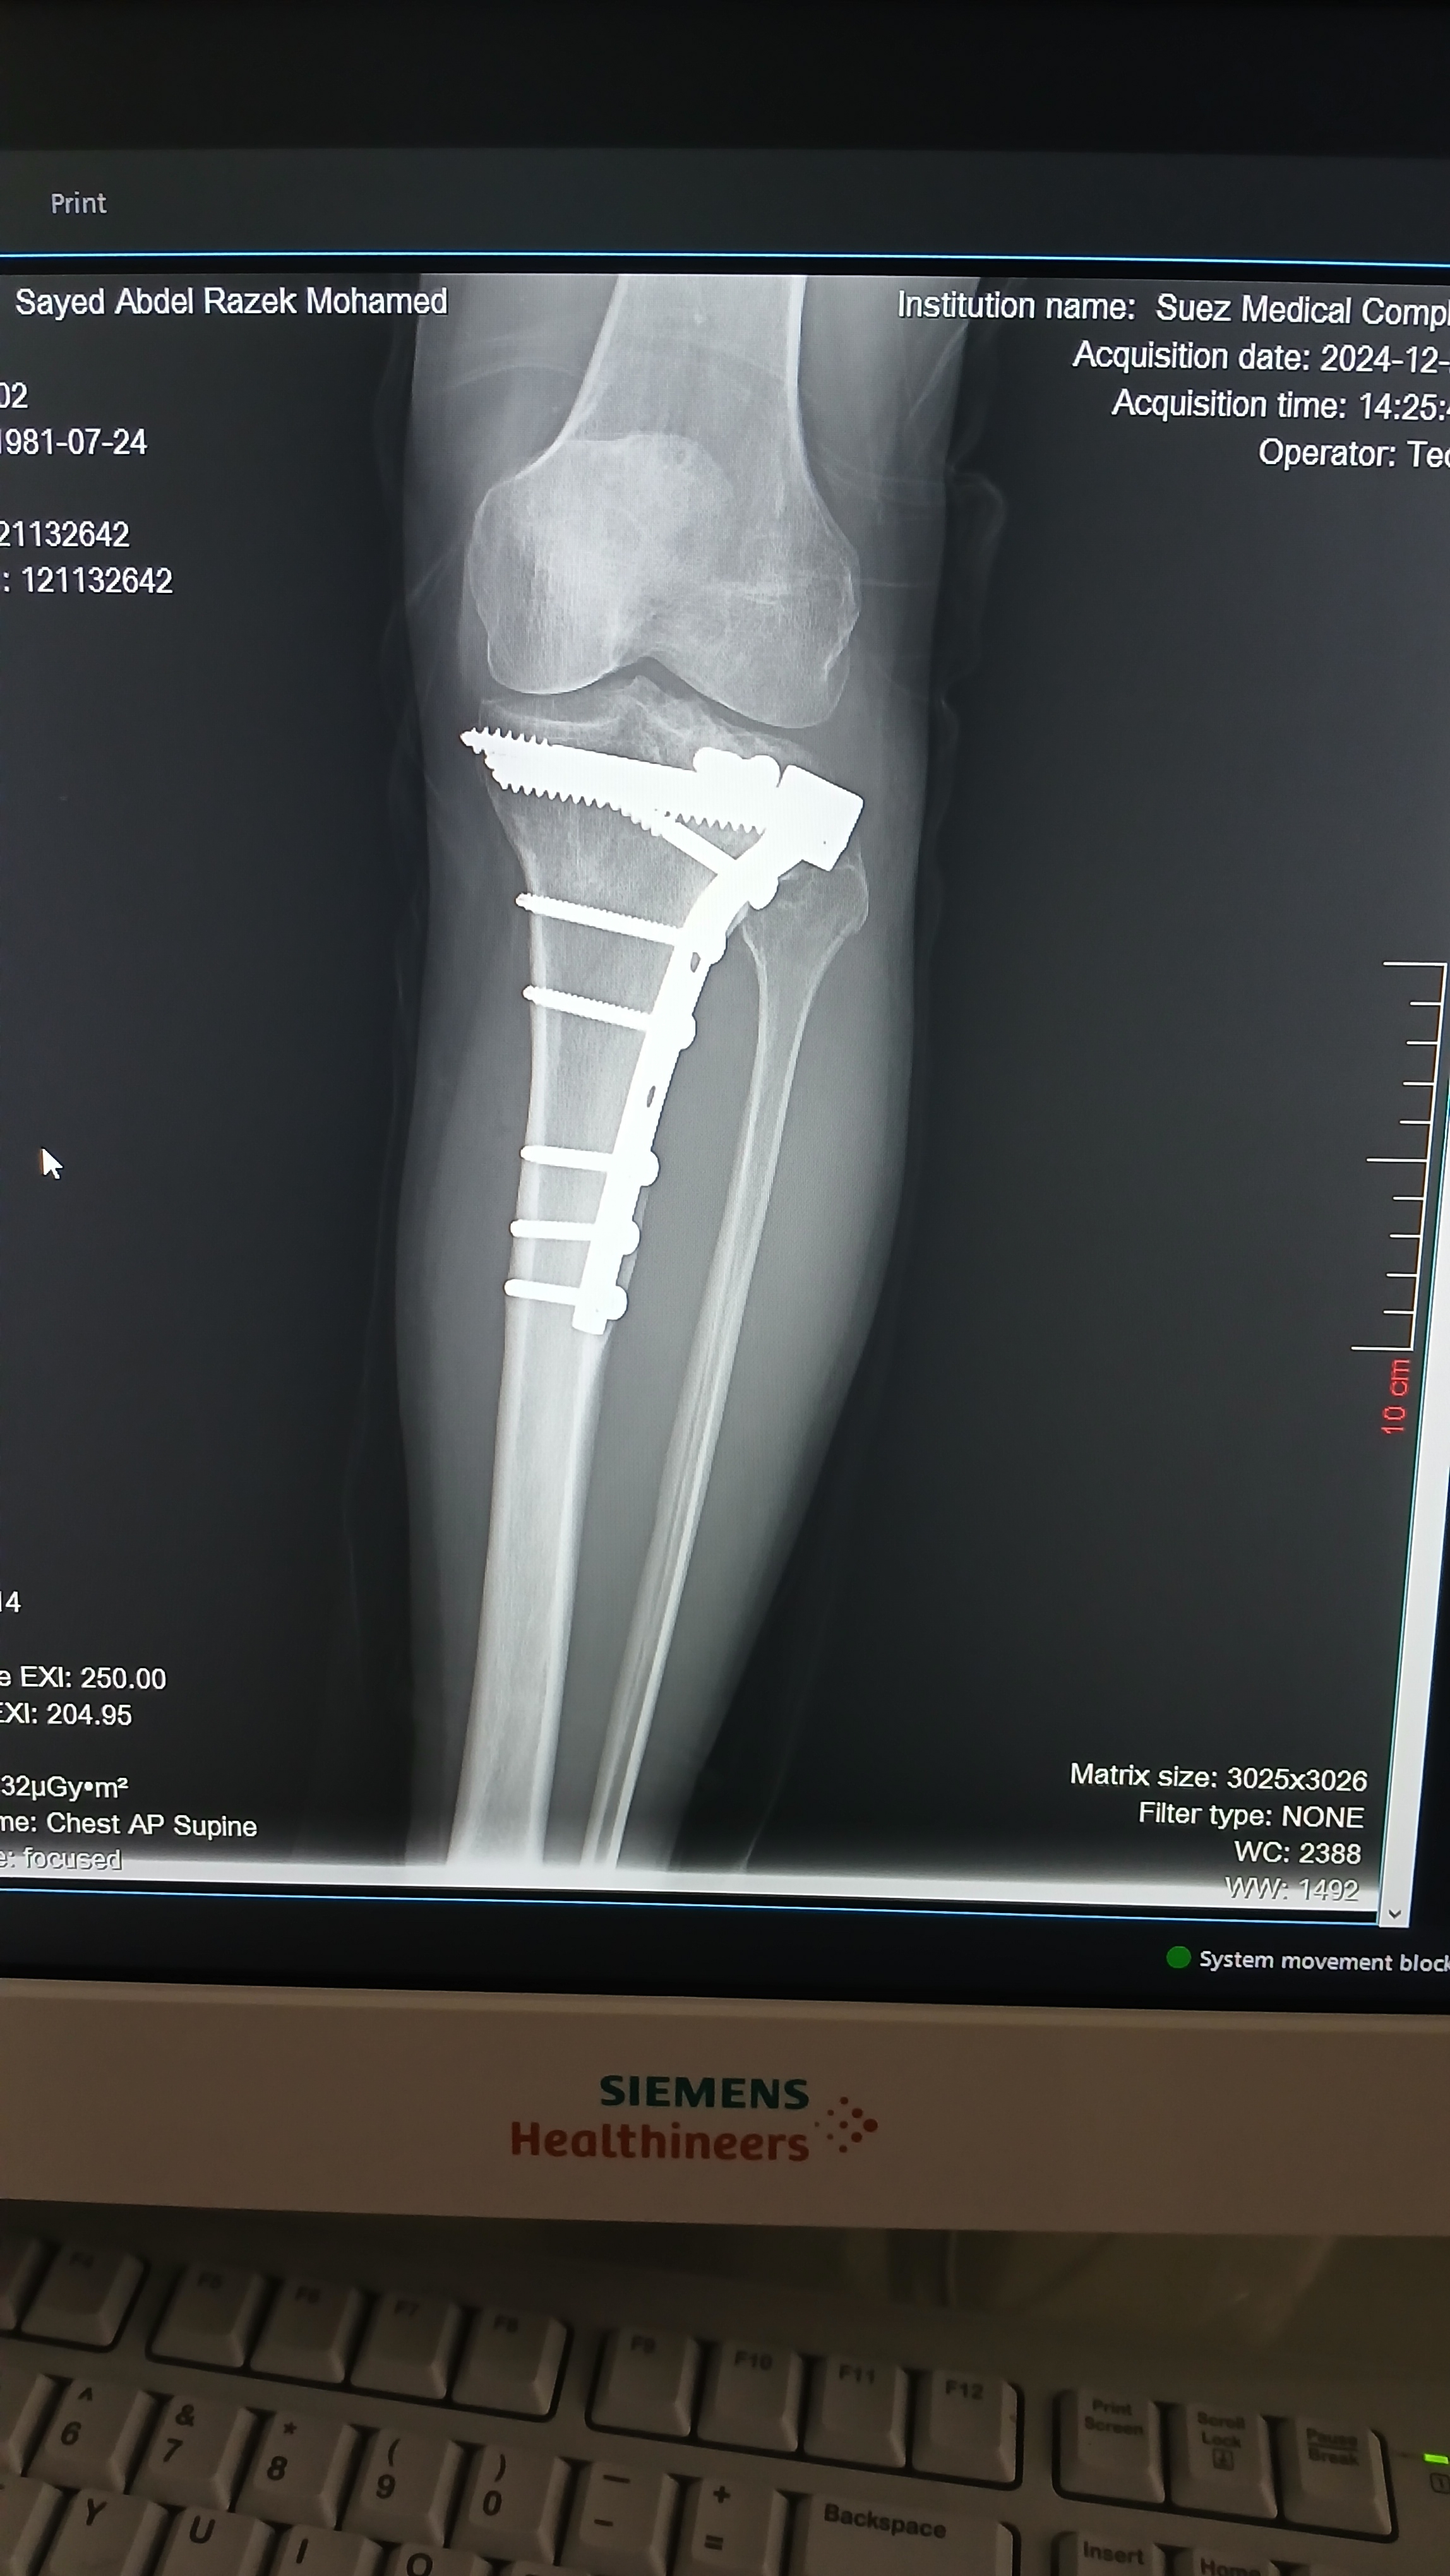

هل يوجد فرق بين صورتي الأشعة؟

كنت عاوز اعرف من دكتور عظام وأشعة في فرق بين الصورتين دي الاشعه قديمه وجديده مع بعض.

دي صورتين القديمه والجديده